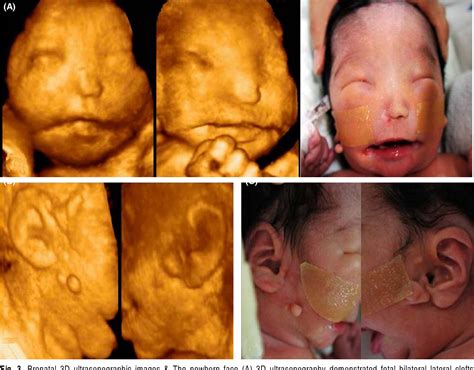

Bilateral cleft palate lip is typically diagnosed during pregnancy through prenatal ultrasound. However, in some cases, the condition may not be detected until after birth. The diagnosis is usually confirmed through a physical examination by a healthcare provider. Additional tests, such as a genetic evaluation, may be recommended to identify any underlying genetic syndromes.

Bilateral cleft palate lip is a type of orofacial cleft, which is one of the most common birth defects. It occurs when the tissues that form the lip and palate do not join together properly during the early stages of pregnancy. This results in openings or clefts on both sides of the lip and palate, which can affect feeding, speech, and hearing.

Clefts can vary in severity, ranging from a small notch in the lip to a complete separation of the lip and palate. Bilateral cleft palate lip is more complex than unilateral clefts, as it involves both sides of the face. This condition can have significant impacts on a child's development, including difficulties with feeding, speech, and social interactions.